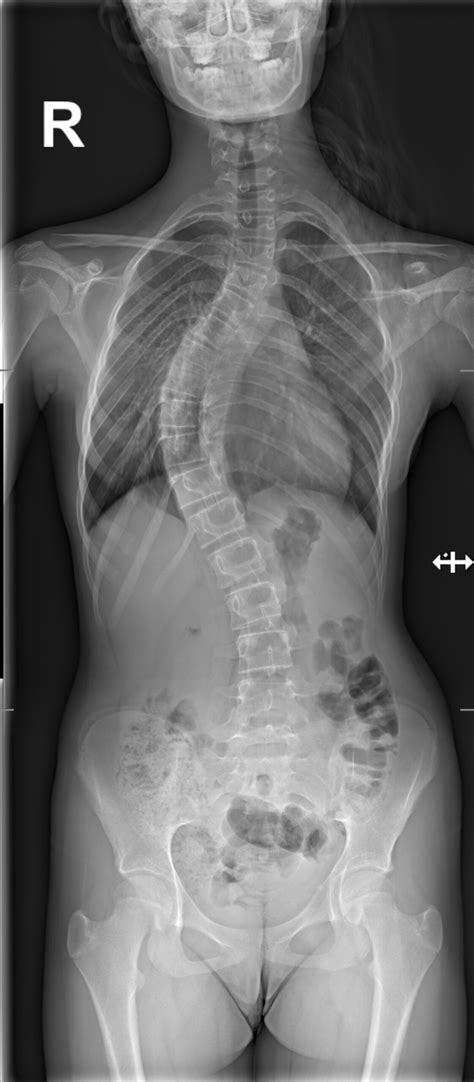

En términos médicos simples, la escoliosis es una desviación lateral de la columna vertebral que hace que esta se curve hacia los lados, formando una figura en "S" o en "C", en lugar de seguir una línea recta vertical. Esta condición puede variar desde una curvatura leve hasta casos graves que requieren intervención médica significativa.

Si notas alguna de estas características en ti o en un familiar, es recomendable programar una cita con un ortopedista para un examen físico completo y una radiografía, que es el estándar de oro para confirmar el diagnóstico.

Para curvas leves (generalmente menores a 25 grados), los médicos suelen recomendar revisiones periódicas con radiografías cada 4 a 6 meses para monitorear si la curva empeora durante el crecimiento del paciente.

Este es el tratamiento estándar para niños y adolescentes con curvas moderadas (entre 25 y 45 grados). El corsé no “cura” la escoliosis, pero actúa como una herramienta para prevenir que la curva siga avanzando mientras el paciente termina de crecer.

Reservada generalmente para curvas severas (mayores a 45-50 grados) o aquellas que afectan la función pulmonar o cardíaca. La cirugía (fusión espinal) busca corregir la curva y estabilizar la columna de forma permanente.